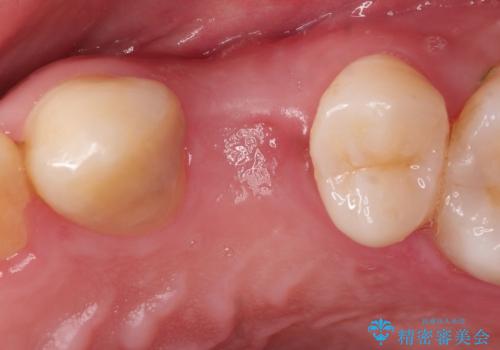

長い間虫歯を放置していたため、根っこだけになっている状態でした。このままでは被せ物を被せられないため抜歯を行い治癒を待った後にインプラントを埋入しオールセラミッククラウンで治療を行いました。